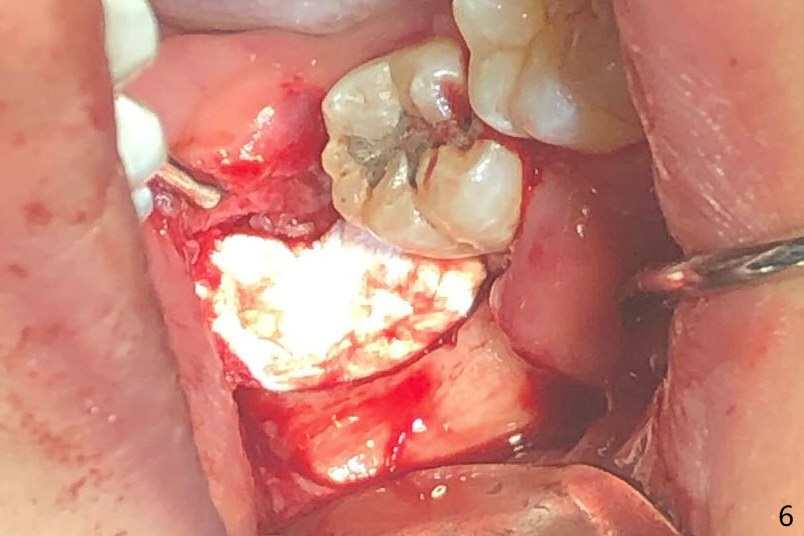

A 22-year-old man with poor oral hygiene requests extraction of the lower right 3rd molar. The buccal gingiva of the 2nd molar is erythematous and edematous (Fig.1 *). There is tenderness between #31 and 32 with severe bone loss (Fig.2 *). After extraction and debridement (Fig.3), Osteogen plug is inserted into radicular portion of the socket (Fig.4 white outline), while allograft is placed coronally (Fig.5, 7), covered by Collagen plug (Fig.6) before suturing. The bone fills the whole socket 1 year postop (Fig.8); there is no root surface exposure at #31. The bone fills the whole socket of #32 one year postop (Fig.8); there is no root surface exposure at #31.